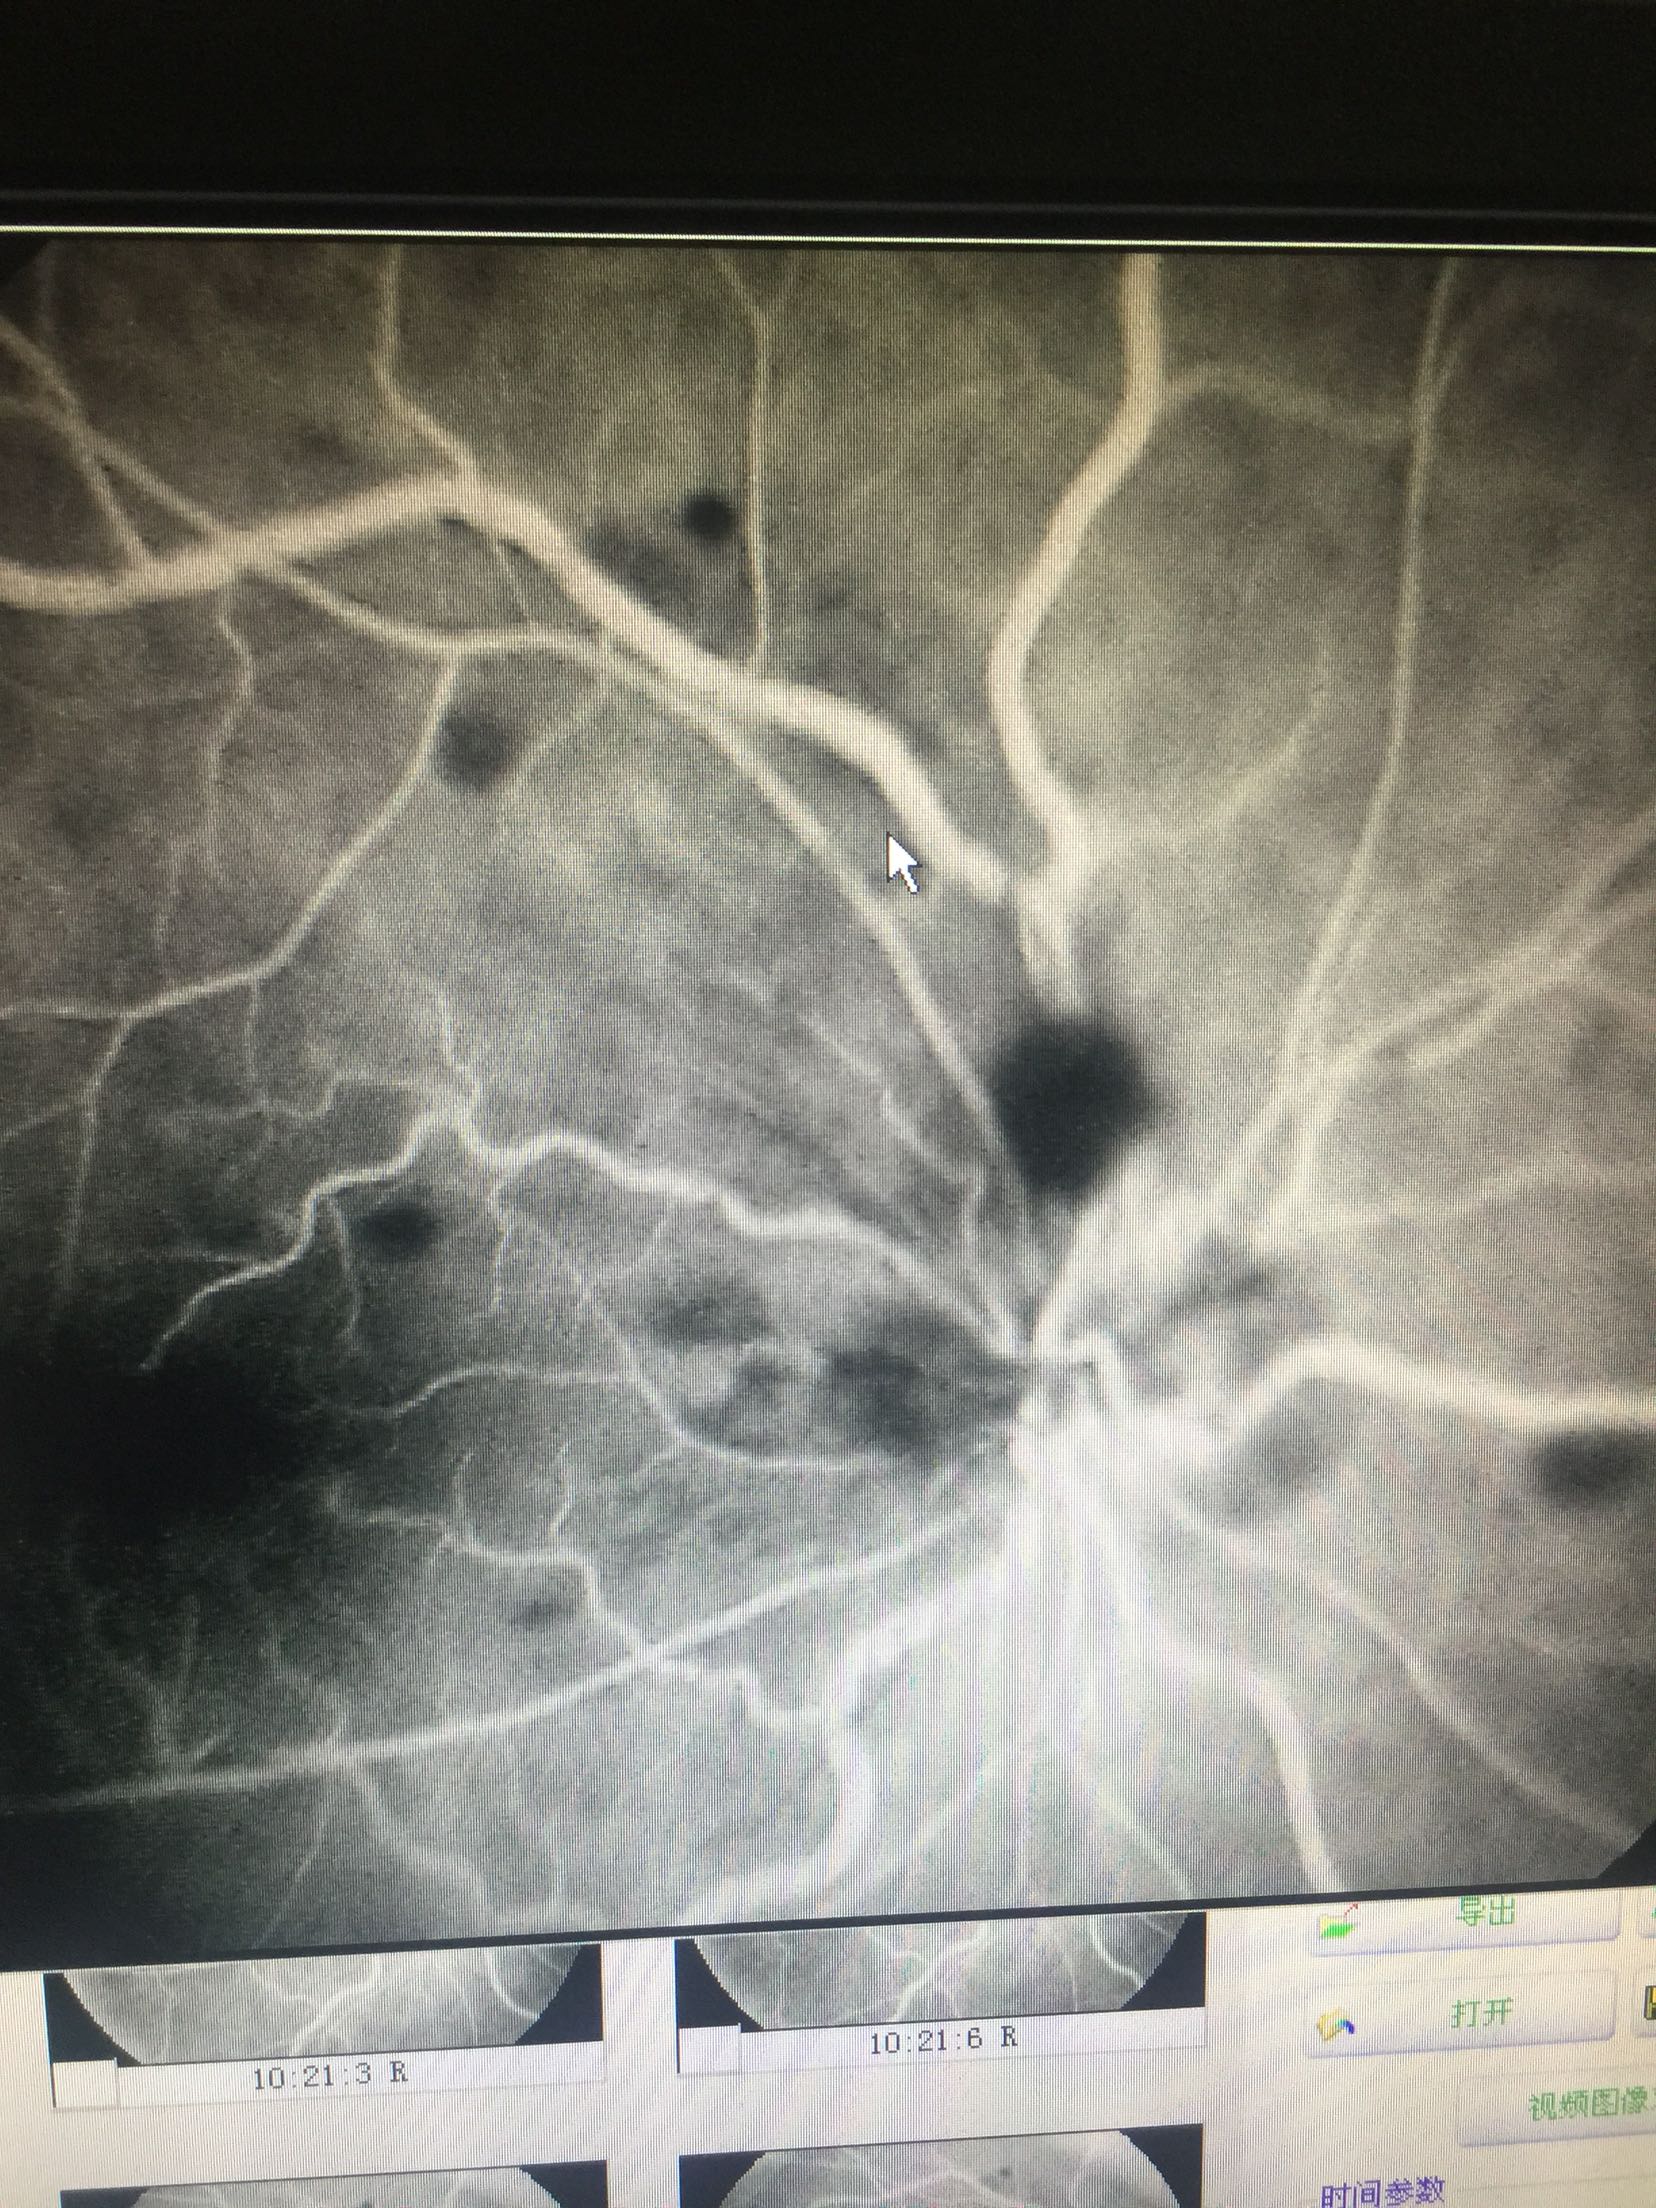

右眼:指数,左眼:0.15 双眼眼睑肤色正常,无红肿,结膜无充血,角膜透明,前房中深,瞳孔正大等圆,虹膜纹理清,晶体无浑浊,右眼眼底可见视盘出血水肿,边界不清,静脉迂曲扩张,黄斑区水肿出血,网膜散在片状出血,

右眼CRVO 扩张血管,营养神经治疗,眼底注射抗VEGF药

这种情况,很难有特别有效的预防手段,主要是规范生活习惯,避免劳累,饮食清淡。 眼底中央静脉阻塞引起的眼底出血,待出血吸收后,视力一般都会有进一步的提高的,但是要特别注意眼底新生血管增生的情况的,如果增生明显,会明显影响视力的,待出血吸收后,一定要做眼底造影明确的,必要时需要激光治疗的。